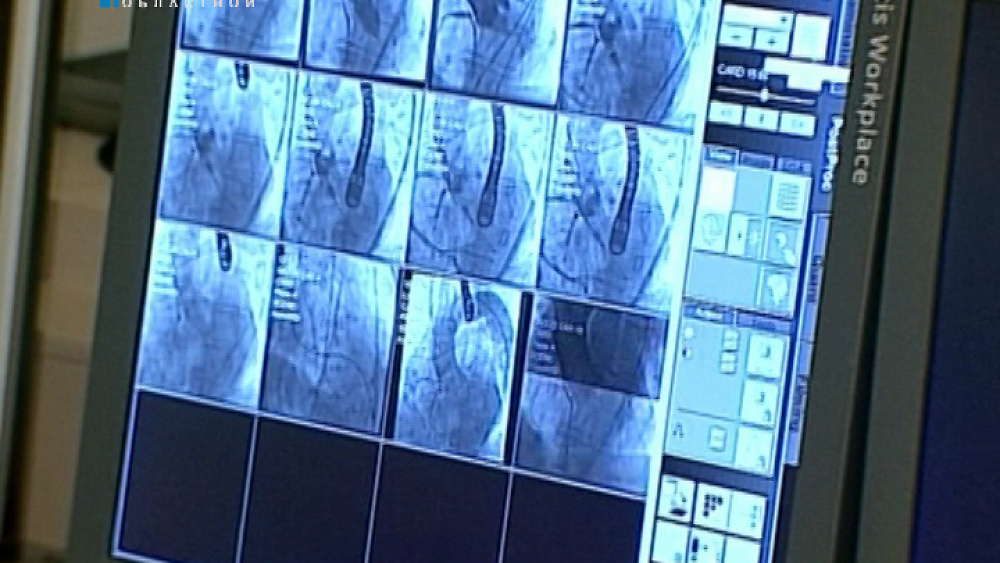

Вздохнули полной грудью и забыли про одышку. Пациентам федерального кардиоцентра в Челябинске делают сложнейшие операции на сердце. Через крохотный разрез хирурги заменяют изношенный клапан аорты на протез. Только за один день медики вживили клапаны-импланты пяти пациентам. А в очереди стоят еще 50 человек. Такая помощь нужна тем, кто не перенесёт традиционные - открытые операции. Подробности - в нашем сюжете.